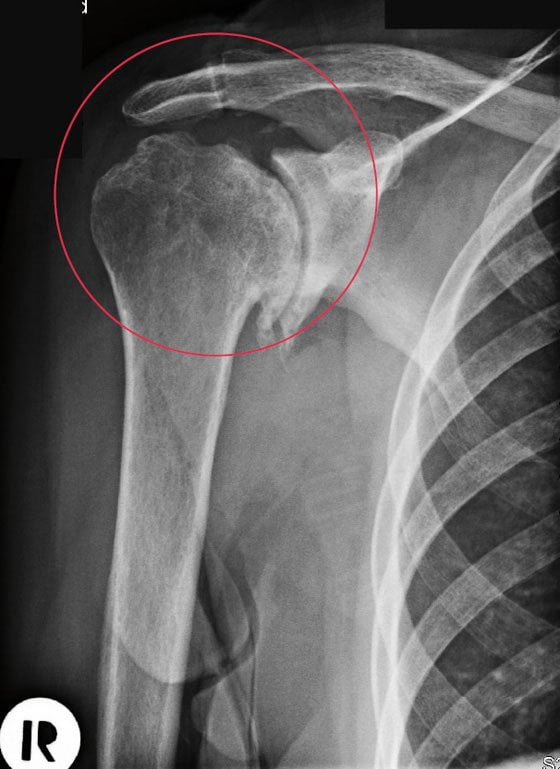

| Рентгенография | Наиболее простой и доступный метод диагностики. Позволяет исключить повреждения костных структур, вывихи, переломы и т. д. Не дает информации о состоянии мягких тканей | При остром воспалении ПС на рентгенограммах обычно отсутствуют какие-либо изменения.У лиц с адгезивным капсулитом и хроническим тендинитом при обследовании могут выявлять остеопороз или кальцификацию околосуставных структур |